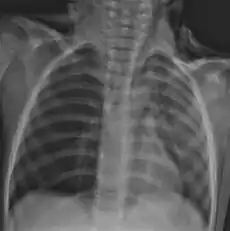

Foreign body in the esophagus causing airway compromise.